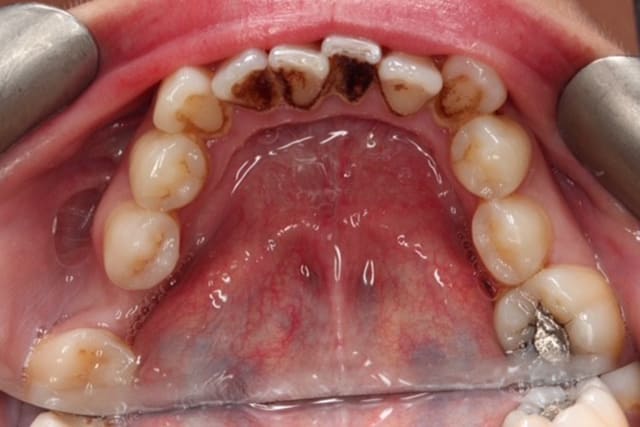

Build up of plaque, calculus and germs on the teeth causes a whole range of dental and general health problems. Bad breath (halitosis), gingivitis (gum inflammation) and periodontitis (irreversible gum disease) are some of the common dental problems that affect people. Dental hygienist can help with prevention or stabalising the gingivitis, bad breath and more serious issues like irreversible gum disease, known as periodontitis. Treatment by dental hygienist can also improve the the general health of a person by reducing the risk of developing heart diseases and Alzheimer’s disease.

If you get the feeling that your teeth and gums are not as clean as they could be even though you have just brushed them, you are probably right. It is time to consult a dental hygienist. Plaque is a nearly colourless film that constantly forms on your teeth. Formed from salivary proteins, bacteria and partly digested food particles, it lies hidden in hard to reach places between your teeth and gums.

Plaque bacteria make your gums tender and swollen, which eventually leads to chronic gum disease. If left untreated, this can progress to the loss of the bone which holds the teeth firmly in the jaws. This can lead to loosening and loss of the affected teeth.